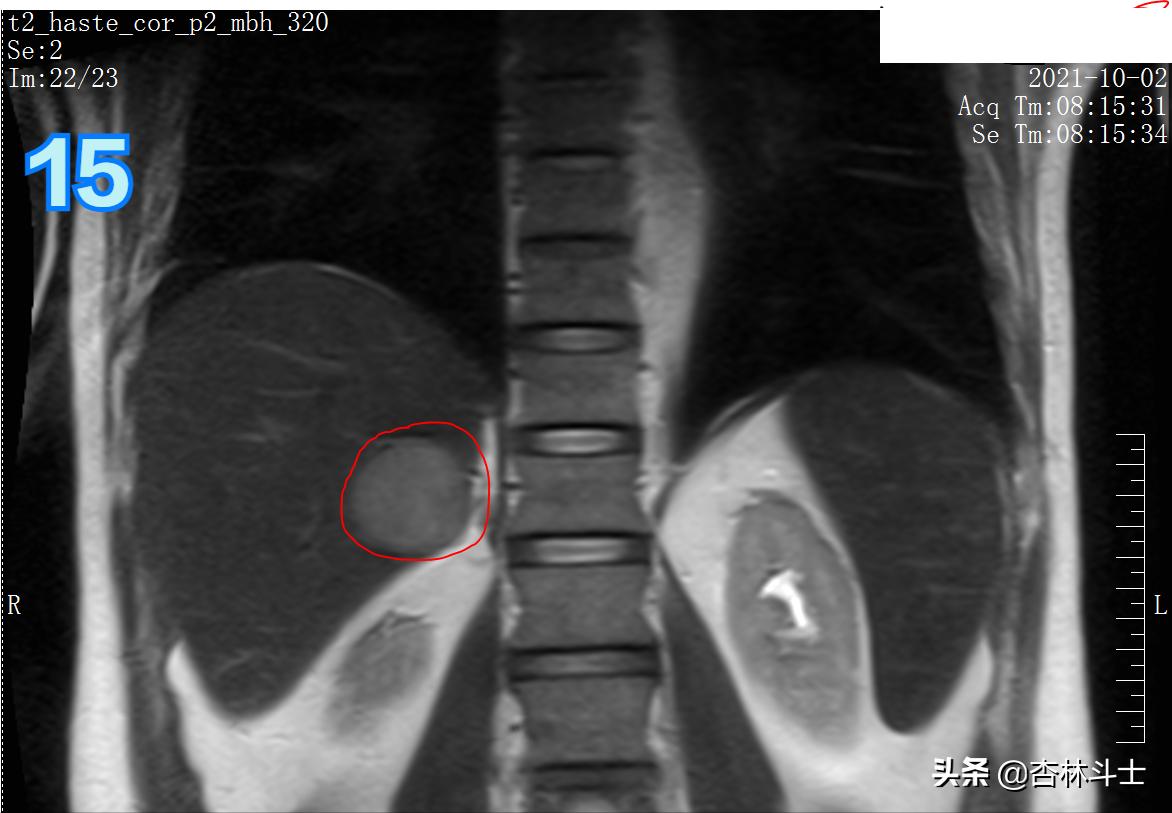

T2冠状位

图14中 1、肝脏 2、双肾 3、脾 4、胸椎椎体 5、椎间盘 6、皮下脂肪 7、胸主动脉 8、膈肌

总结:10月份复查,肝右后叶下段新发一个直径约1㎝的结节,T1呈等信号,T2呈稍高信号,弥散加权序列可见弥散明显受限,增强动脉期明显均匀强化,门静脉期出现对比剂廓清,呈略低信号,平衡期信号进一步减低,肝胆特异期未见特异性对比剂摄取呈低信号。增强特征为典型的“快进快出”,影像学上典型的肝细胞癌表现。